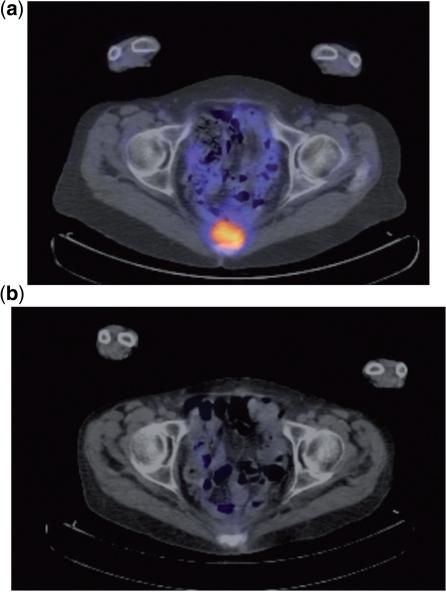

Radical resection is the only potential cure for patients with locally advanced primary and recurrent rectal cancer and is considered curative only when the histologic margins are clear of tumour. Early diagnosis of the disease is essential as it increases the likelihood of a potentially curative resection and prevention of dissemination. Clinical examination, tumour markers and radiologic modalities such as ultrasonography, computed tomography, magnetic resonance imaging and positron emission tomography are routinely used in an effort to accurately stage these patients and provide useful information for the selection of patients for further treatment/management. This review describes the methods of staging patients with locally advanced primary and recurrent rectal cancer prior to surgery emphasizing the role that radiologists have in this process.

根治性切除术是局部晚期原发性和复发性直肠癌患者的唯一潜在治愈方法,只有当组织学切缘无肿瘤时才被认为是治愈性的。早期诊断疾病至关重要,因为这增加了潜在治愈性切除的可能性,并防止了疾病的扩散。临床检查、肿瘤标志物和影像学方式,如超声、计算机断层扫描、磁共振成像和正电子发射断层扫描,通常用于准确分期这些患者,并为进一步治疗/管理的患者选择提供有用的信息。本综述描述了在手术前对局部晚期原发性和复发性直肠癌患者进行分期的方法,强调了放射科医生在这一过程中的作用。